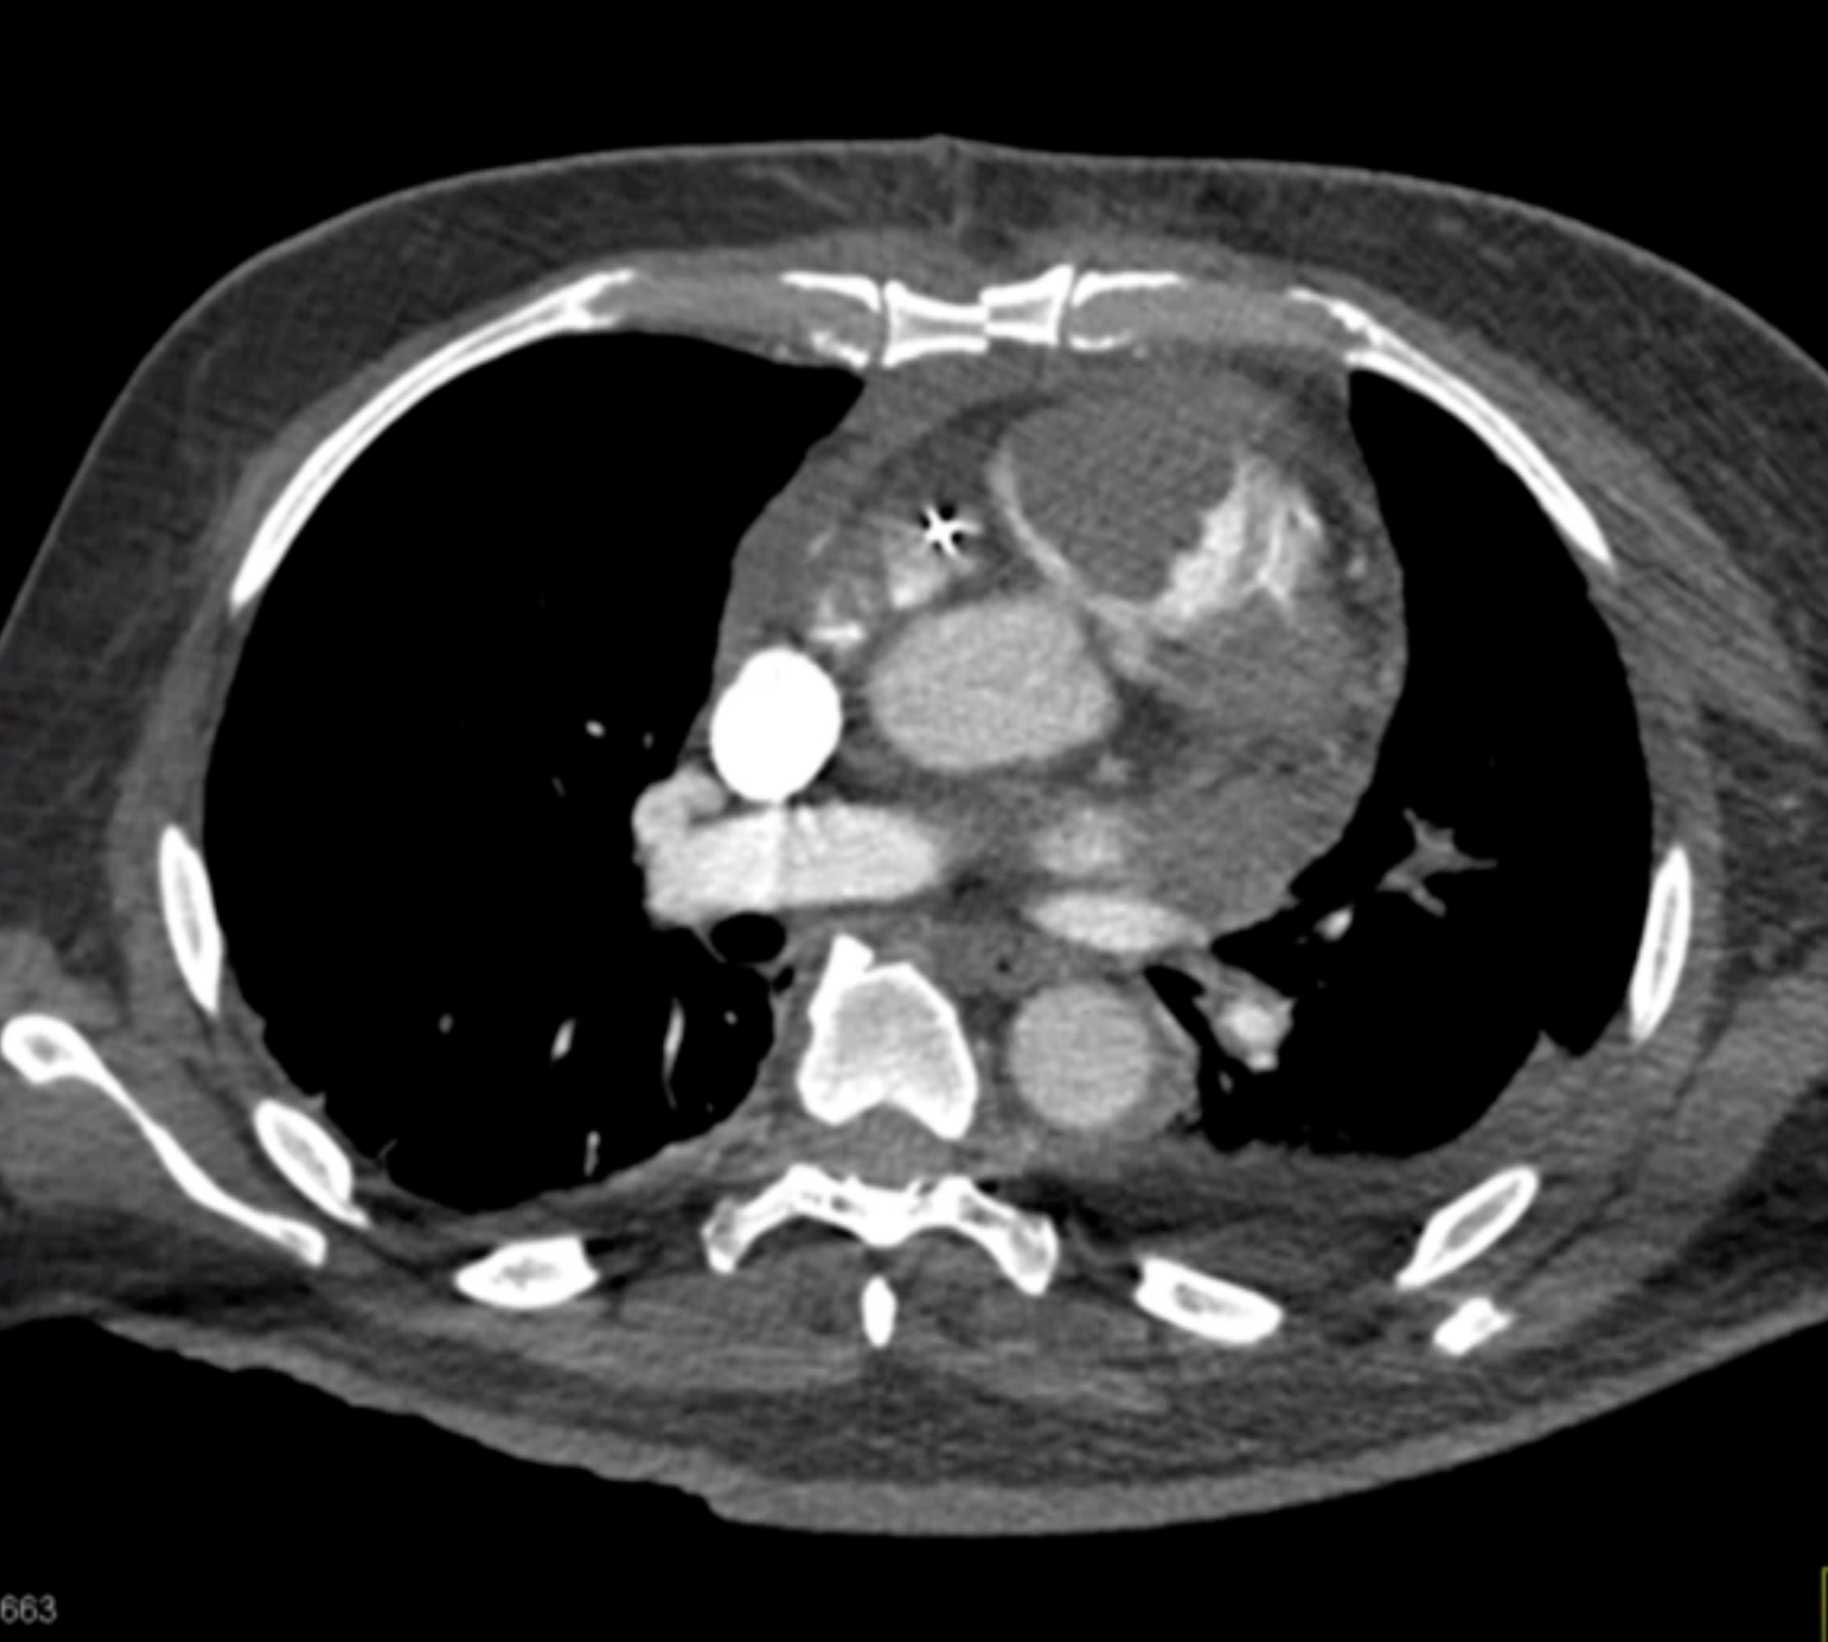

Primary Spindle Cell Carcinoma of the Right Ventricle